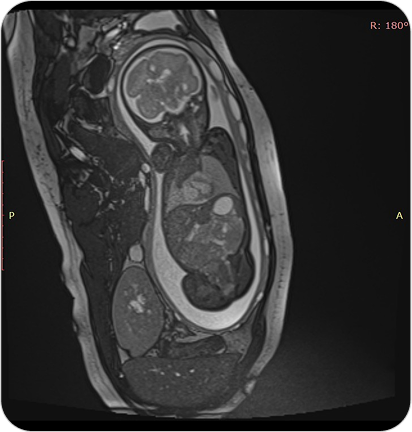

Resonancia Magnética Fetal

La resonancia fetal es un estudio no invasivo que permite observar con gran detalle el desarrollo del bebé en el útero. Es un complemento ideal de la ecografía cuando se necesita información más precisa.

La resonancia magnética fetal permite obtener imágenes detalladas del bebé durante el embarazo, sin utilizar radiación. Se utiliza como complemento del ultrasonido cuando se detectan hallazgos que requieren evaluación más precisa.

¿PARA QUE SE UTILIZA?

- Evaluar el desarrollo del sistema nervioso central fetal (cerebro y médula espinal).

- Detectar malformaciones cerebrales o anomalías estructurales.

- Valorar la anatomía de órganos internos en casos complejos.

- Confirmar o descartar hallazgos dudosos en ecografías.

- Planificar tratamientos o decisiones perinatales junto con el equipo obstétrico.

¿POR QUÉ ES UN ESTUDIO DESTACADO?

- No invasivo y seguro para la madre y el bebé.

- Alta definición de imágenes incluso en embarazos avanzados.

- Permite tomar decisiones médicas informadas y personalizadas.

- Evita resonancias post-natales.

Resonancia Magnética Fetal

La resonancia fetal es un estudio no invasivo que permite observar con gran detalle el desarrollo del bebé en el útero. Es un complemento ideal de la ecografía cuando se necesita información más precisa.

La resonancia magnética fetal permite obtener imágenes detalladas del bebé durante el embarazo, sin utilizar radiación. Se utiliza como complemento del ultrasonido cuando se detectan hallazgos que requieren evaluación más precisa.

¿PARA QUE SE UTILIZA?

- Evaluar el desarrollo del sistema nervioso central fetal (cerebro y médula espinal).

- Detectar malformaciones cerebrales o anomalías estructurales.

- Valorar la anatomía de órganos internos en casos complejos.

- Confirmar o descartar hallazgos dudosos en ecografías.

- Planificar tratamientos o decisiones perinatales junto con el equipo obstétrico.

¿POR QUÉ ES UN ESTUDIO DESTACADO?

- No invasivo y seguro para la madre y el bebé.

- Alta definición de imágenes incluso en embarazos avanzados.

- Permite tomar decisiones médicas informadas y personalizadas.

- Evita resonancias post-natales.